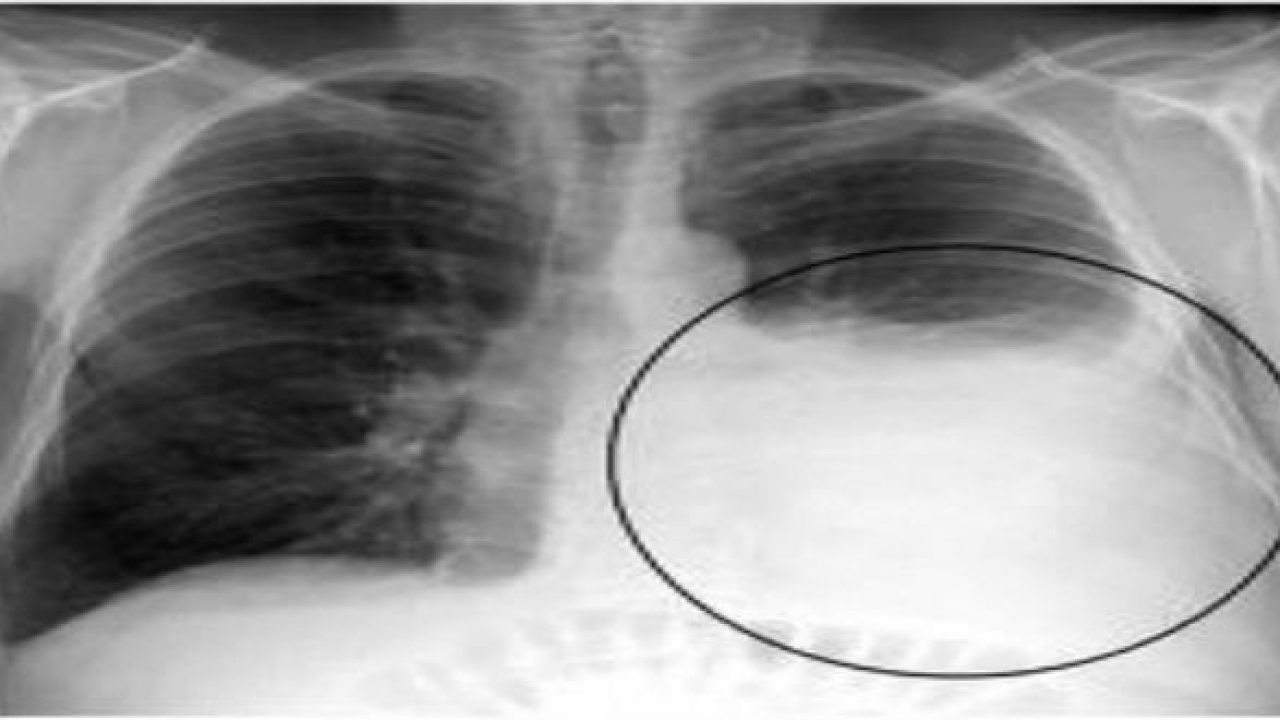

- Viêm thanh quản: thanh quản là đường dẫn khí duy nhất vào đường hô hấp dưới, khi thanh quản bị viêm có thể gây phù nề niêm mạc vùng thanh quản và dây thanh âm làm hẹp và bít đường thở gây suy hô hấp

- Nặng hơn nữa có thể dẫn đến Hội chứng suy hô hấp cấp: khó thở, NT > 30l/phút, co kéo cơ hô hấp phụ, …